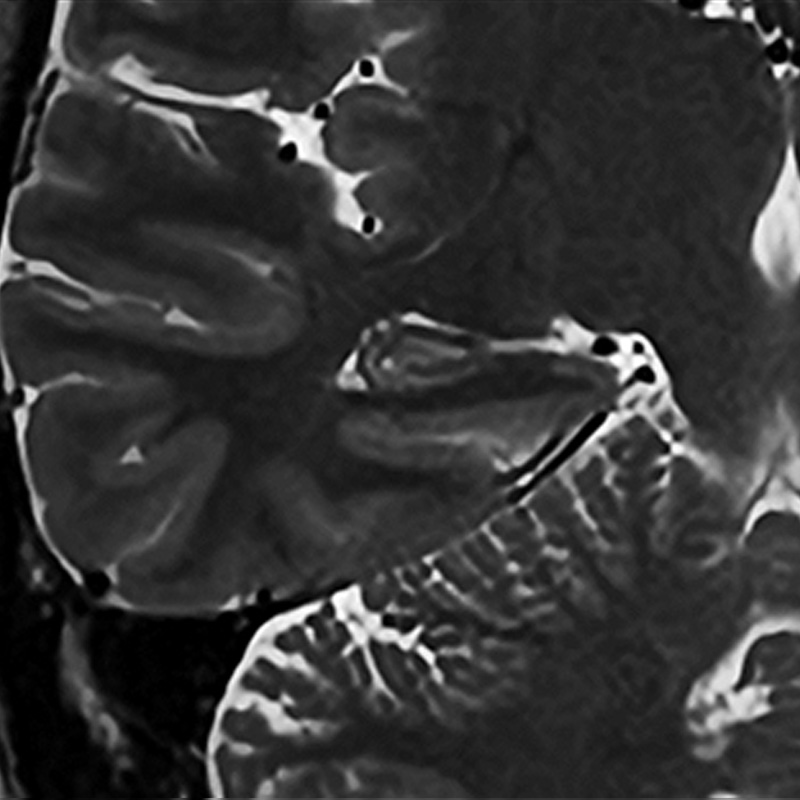

Cor T2w for hippocampus

Example of a high-resolution image of the hippocampus using Precise IQ Engine (PIQE). The original image is 256 matrix with low resolution and high signal-to-noise ratio (SNR).

Even though the scan time is reasonably short and the slice thickness is as thin as 2 mm, the image is clear and demonstrates good contrast.